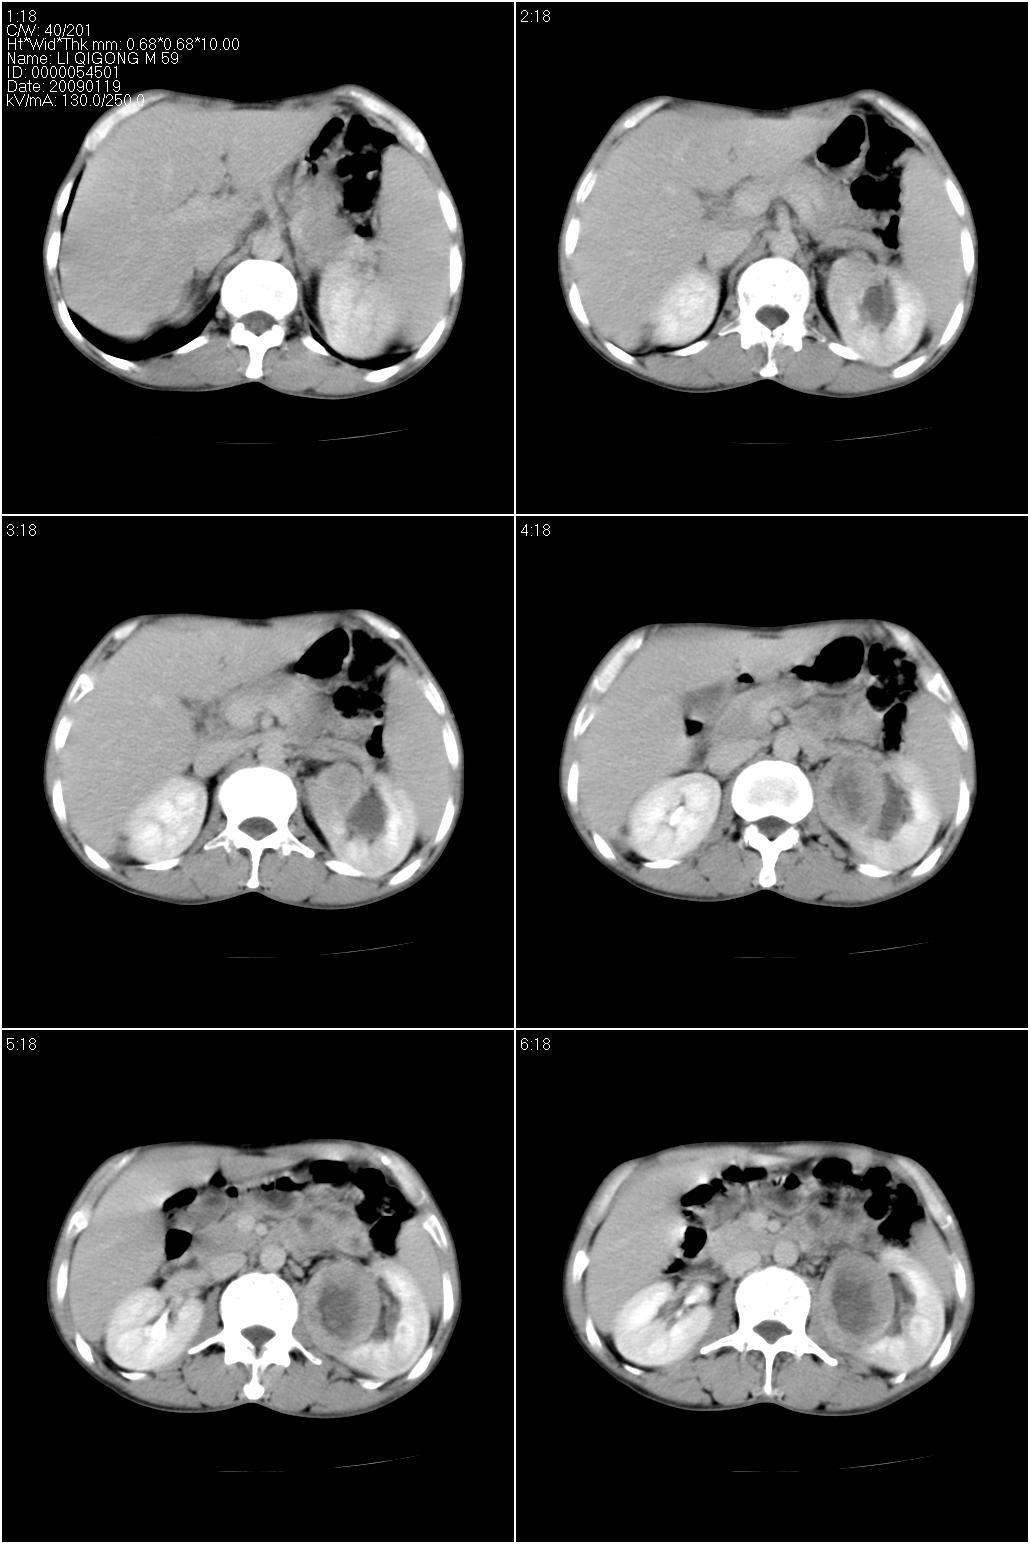

男性,59岁。体检发现左肾占位。自诉无尿血、尿痛。

无痛无血尿,左肾实质占位,有明显强化,中心坏死不规则,应该肾癌无疑。

应该考虑左肾癌并肾盂积水

诊断依据:

1、中老年男性.

2、左肾占位,呈不均匀性强化,中央有无强化的坏死区。

3、左肾门旁有侧枝开放,提示左肾静脉癌栓形成可能。

4、患者自诉无血尿,但不一定镜下无血尿。